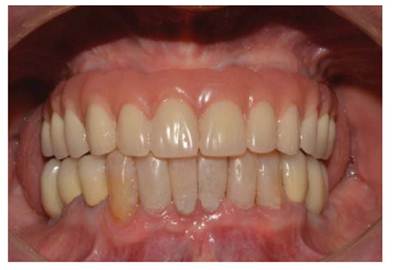

Luego se procedió a la fabricación de la estructura metálica del maxilar superior con la ayuda de una pantalla de silicona obtenida del protocolo reverso, esta estructura presentó un asentamiento pasivo comprobado clínica y radiográficamente luego de realizar los cortes y soldajes necesarios (Figura 5). Se realizó el enfilado para la prótesis híbrida con dientes Ivostar/Gnathostar donde se evaluó estética y fonación. En el maxilar inferior se torquearon los pilares CM recto para la pieza 35 y Pilares angulados (17°) a nivel de piezas 36 y 46 fresados con la ayuda de una guía de colocación de pilares (Figura 6) y se fabricaron coronas de metal cerámica. Para finalizar se procede a la instalación de la prótesis híbrida superior, la cementación de las coronas con cemento temporal y la instalación de una férula de DCM (figura a y b). Finalizado el tratamiento se realizaron controles periodontales y protésicos periódicos donde se comprobó la correcta concientización del paciente en cuanto a su mantenimiento. (Figura 8)

Es importante considerar que mediante el uso de técnicas predecibles como el protocolo reverso y una adecuada planificación quirúrgica y protésica lograremos la completa satisfacción del paciente tanto en lo funcional como en la estética y fonética.